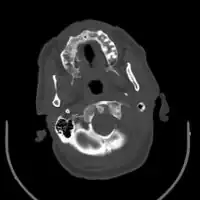

Chronic subdural after treatment with burr holes